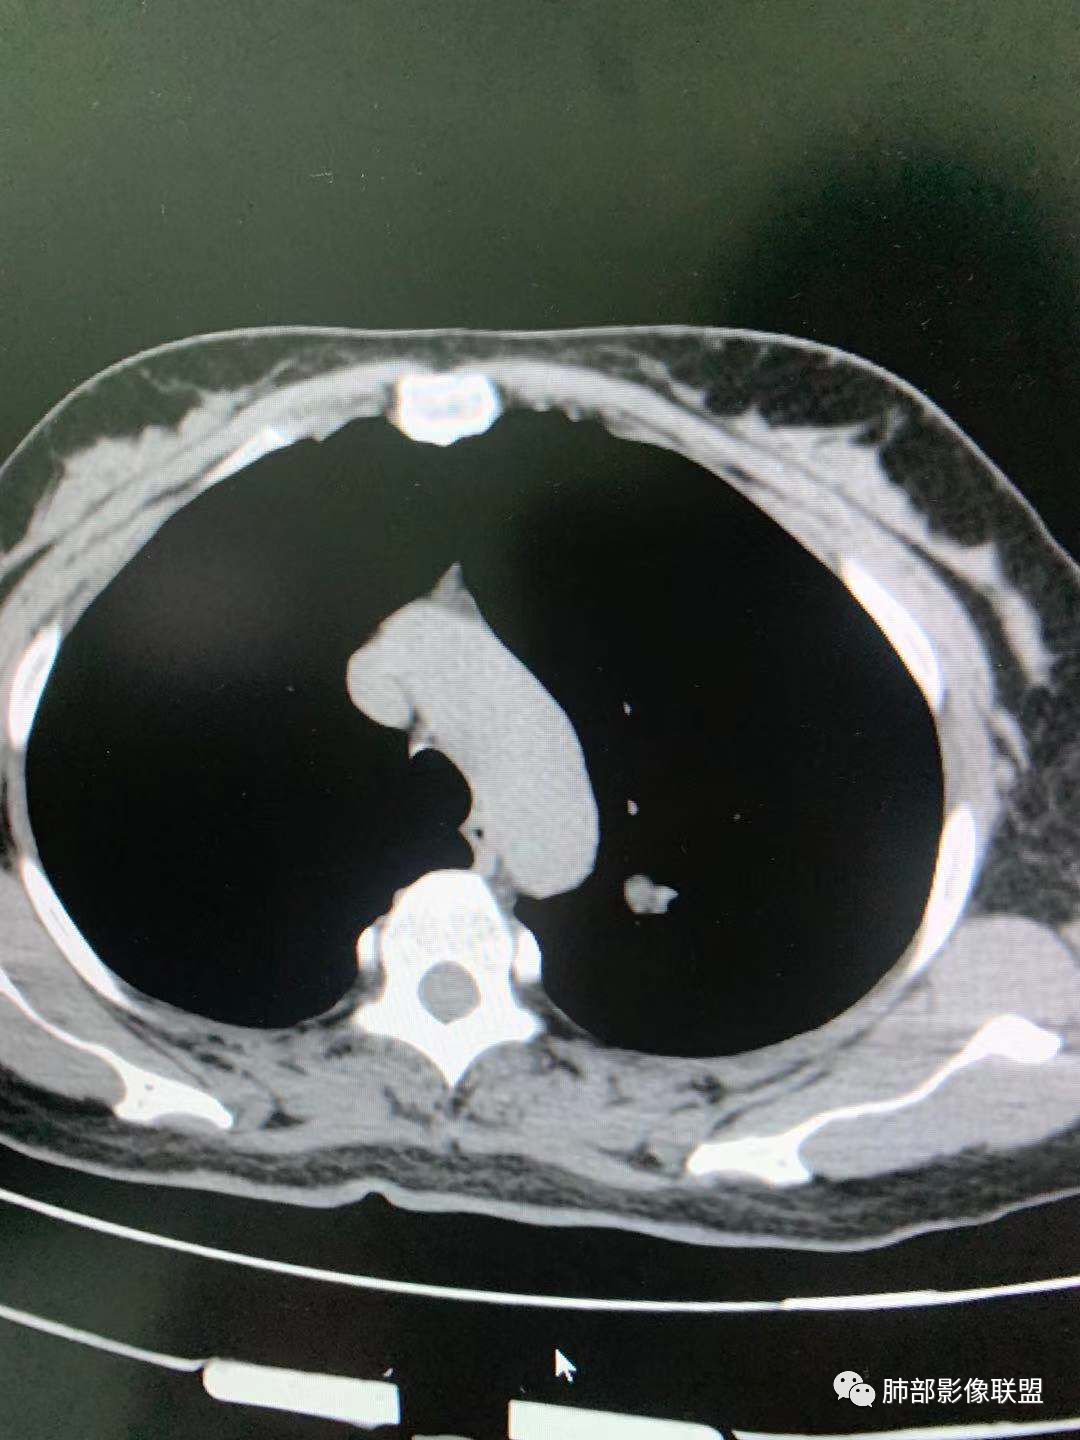

二、看第二个结节

1、密度?

2、边界?

3、收缩力?

4、血管?

5、大小、内部结构、CT值

金豆

纯磨玻璃 边界清

小兜

磨玻璃,边界清

三个石头

纯磨玻璃,能画出轮廓,但是感觉边缘又比较模糊,是层厚原因吗,收缩力弱,血管进入

心灵鸡汤

与左肺上叶纵隔旁pGGN

南边

三、看看这一个

1、密度:PGGN?MGGN?

lmg

这个密度要高一些,混合磨玻璃结节

MGGN,比上面两个密度高

这个结节中间密度稍高一些 不像纯的

二.左肺上叶前段磨玻璃结节:

该结节较大,边界清楚,小叶间隔阻挡特征相当明显,微浸润腺癌的诊断几乎没有争议!

三.右肺上叶胸膜下结节及左肺上叶血管旁结节,尽管都是磨玻璃密度,但都比较小且边缘特征不明显,恶性征象未显露,处置并无特殊,定期复查!